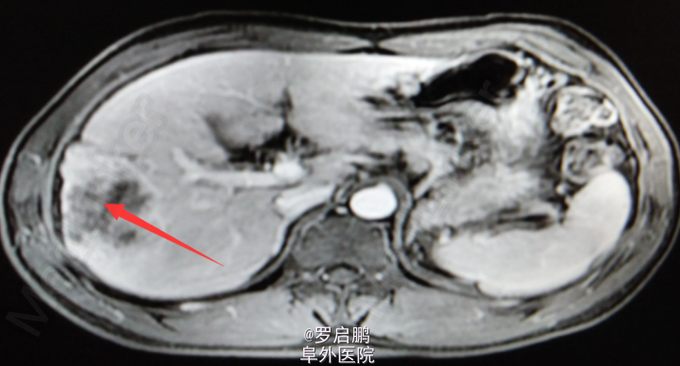

患者 男 48岁 主诉:发现肝脏占位半月 现病史:半月前患者因慢性乙型肝炎复查腹部超声发现右肝占位 既往:慢性乙肝20年,未规律治疗。 个人史:吸烟史25年20支/天,饮酒史13年,白酒2两/次。

超声:右肝高回声光团,胆囊、肝内外胆管、脾脏、双肾未见异常 腹部MRI:肝右叶占位 腹部平扫+增强:肝右叶占位,肝内多发小密度,左肾囊肿,腹膜后淋巴结肿大

肝右叶占位,肝癌? 前入路右半肝切除,LC 鉴别诊断:原发性肝癌;肝转移癌;肝海绵状血管瘤;肝腺瘤;血管平滑肌脂肪瘤。

注意术中循环维持,备血、血浆。术中平稳。术中病理:(右半肝)低分化胆管腺癌,可见坏死,肝内可见多发卫星灶,紧邻肝被膜,切缘未见特殊。术后恢复良好出院。